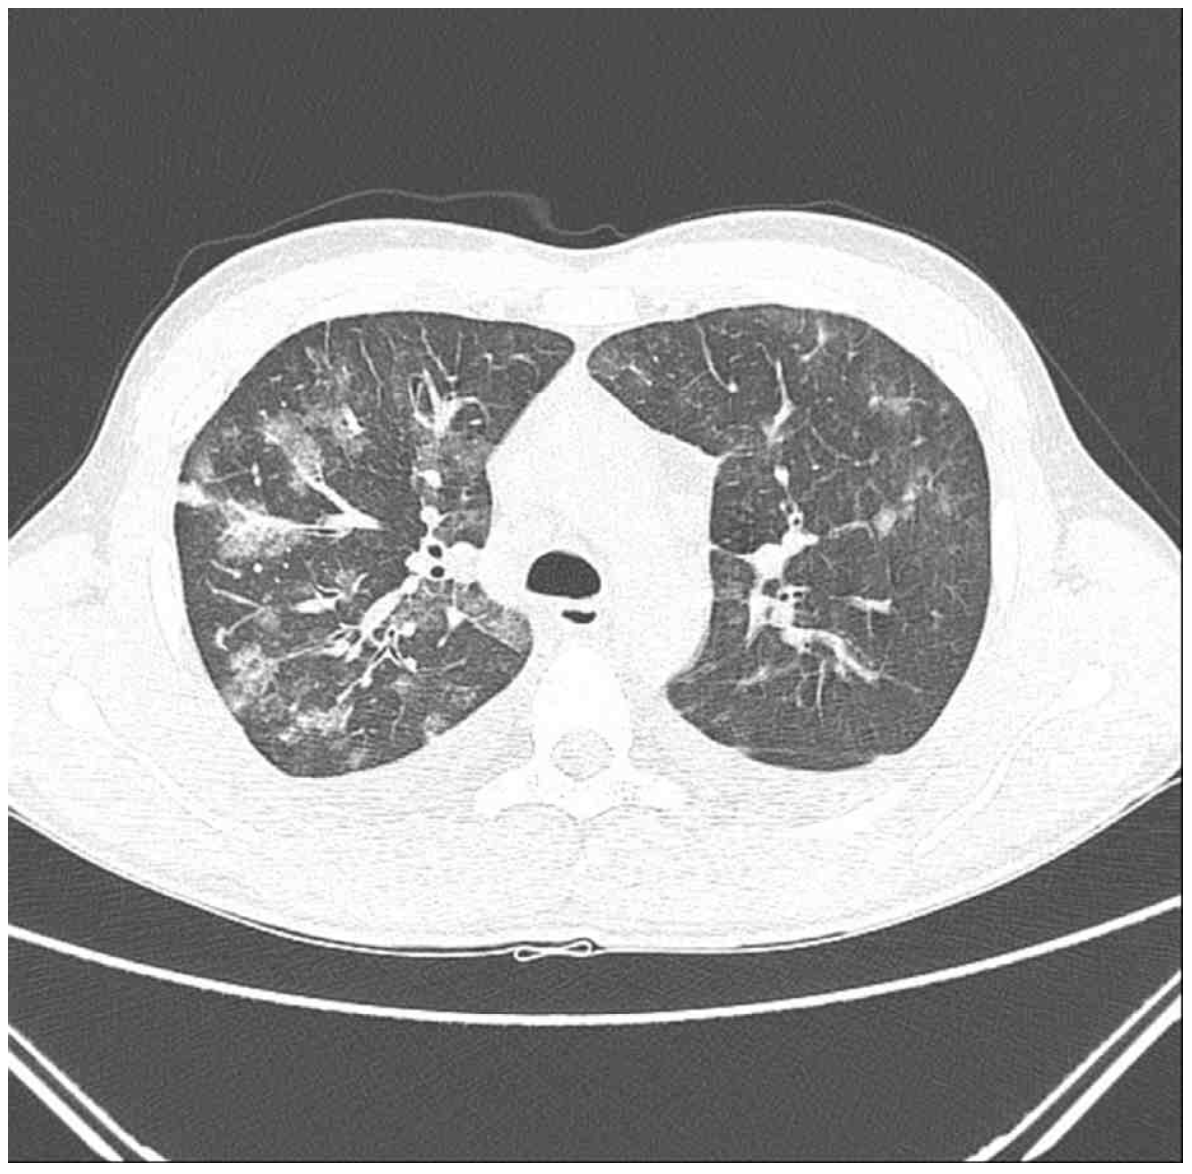

20세 남자가 2일 전부터 기침을 하고 숨이 찬다며 병원에 왔다. 10일 전부터 흡연을 새로 시작하였다. 혈압 124/80 mmHg, 맥박 100회/분, 호흡 22회/분, 체온 37.7℃이다. 양쪽 가슴에서 거품소리가 들린다. 가슴 X선사진, 가슴 컴퓨터단층촬영 사진과 기관지폐포 세척액 파파니콜로 사진이다. 검사 결과는 다음과 같다. 치료는?

CXR, CT: Bilateral multifocal GGO

• CXR 및 chest CT상 multifocal patchy GGO를 양쪽에서 관찰할 수 있으며 혈액검사상 CRP 상승에도 백혈구 수치가 참고치 이내이므로 세균 감염의 가능성은 낮다고 판단할 수 있다. 더불어 말초혈액에서 호산구 수치 역시 5% 이내로 현재 검사 소견만으로는 호산구증가증을 확인할 수 없다.